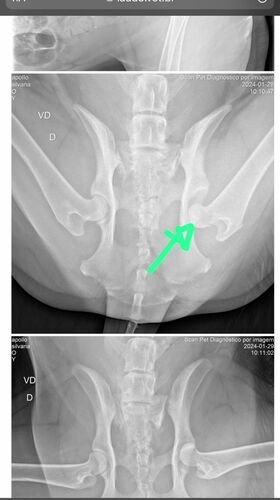

Oi! Meu cachorro Apollo, meu vira-lata com carinha de São Bernardo, foi atropelado por um caminhão neste sábado e está internado desde então. Após o Raio-X feito hoje (29/01), ele foi diagnosticado com luxação coxofemoral, que necessita de uma cirurgia para recolocar o fêmur no local correto. A ausência da cirurgia irá gerar dor crônica nele, além de ocasionar danos irreversíveis como a perda da locomoção, visto que ele não consegue ficar de pé.